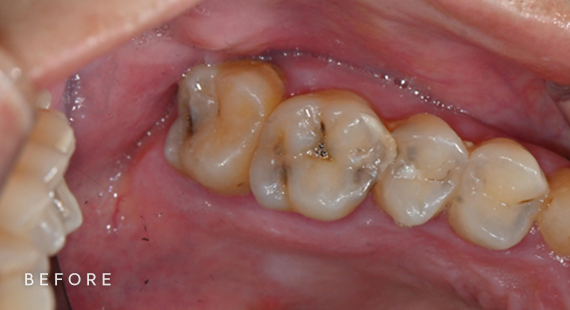

충치치료